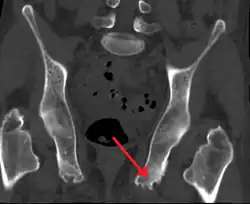

| Enthesopathy of the pelvis likely due to ankylosing spondylitis | |

An enthesopathy refers to a disorder involving the attachment of a tendon or ligament to a bone.[1] This site of attachment is known as the enthesis (pl. entheses). If the condition is known to be inflammatory, it can more precisely be called an enthesitis.